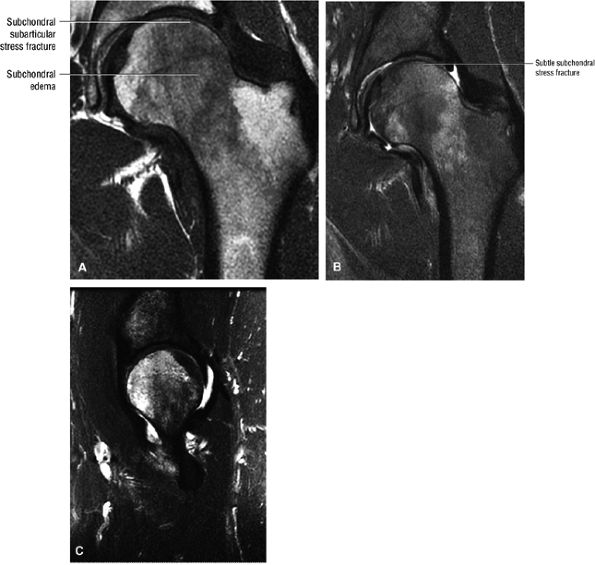

FIGURE 3.98 ● A 40-year-old male patient with subtle subchondral stress fracture easily mistaken for transient osteoporosis. (A) Coronal T1-weighted image. (B) Coronal FS PD FSE image. (C) Sagittal FS PD FSE image.